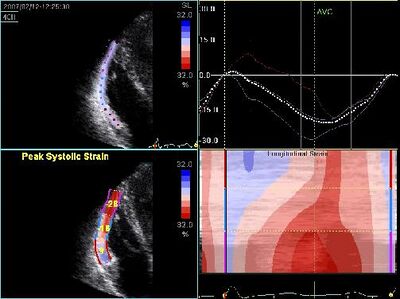

Decreased RV strain in ARVC

Dilated cardiomyopathy (DCM)

• It is the most common form of cardiomyopathy.

• Also known as congestive cardiomyopathy.

• Poor LVF and LV dilatation.

• Arrhythmias (atrial fibrillation 20-30%).

• Clot formation, which may lead to thrombo-embolic complications.

• Often accompanied by pulmonary hypertension, dilation of other compartments, and an insufficiency of mitral and/or tricuspid valve

• Familial DCM's common to autosomal dominant, autosomal recessive and sex-linked inheritance.